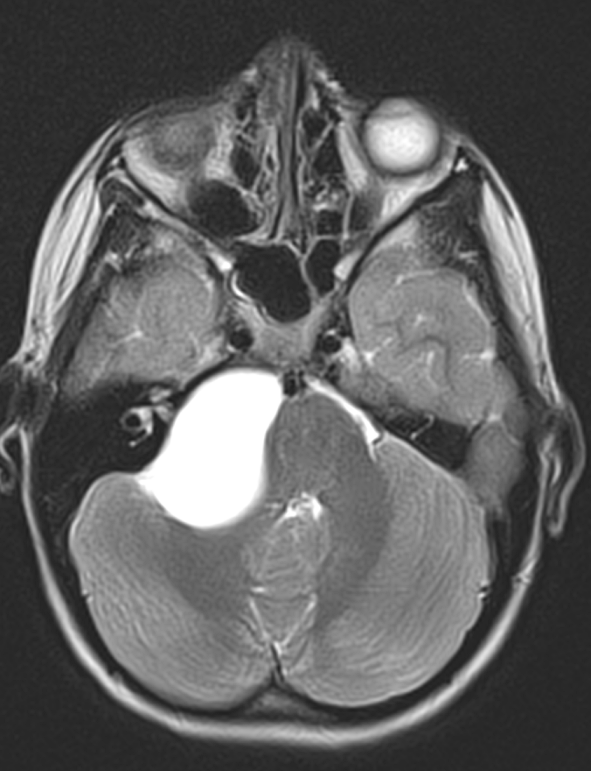

Imagistica este esențială pentru identificarea chistelor arahnoidiene:

- RMN (rezonanță magnetică nucleară): metoda preferată, evidențiază conținutul de LCR și raporturile cu structurile cerebrale.

Chistul arahnoidian apare ca o leziune hipointensă pe imaginile T1 și hiperintensă pe imaginile T2, cu semnal identic cu cel al lichidului cefalorahidian.